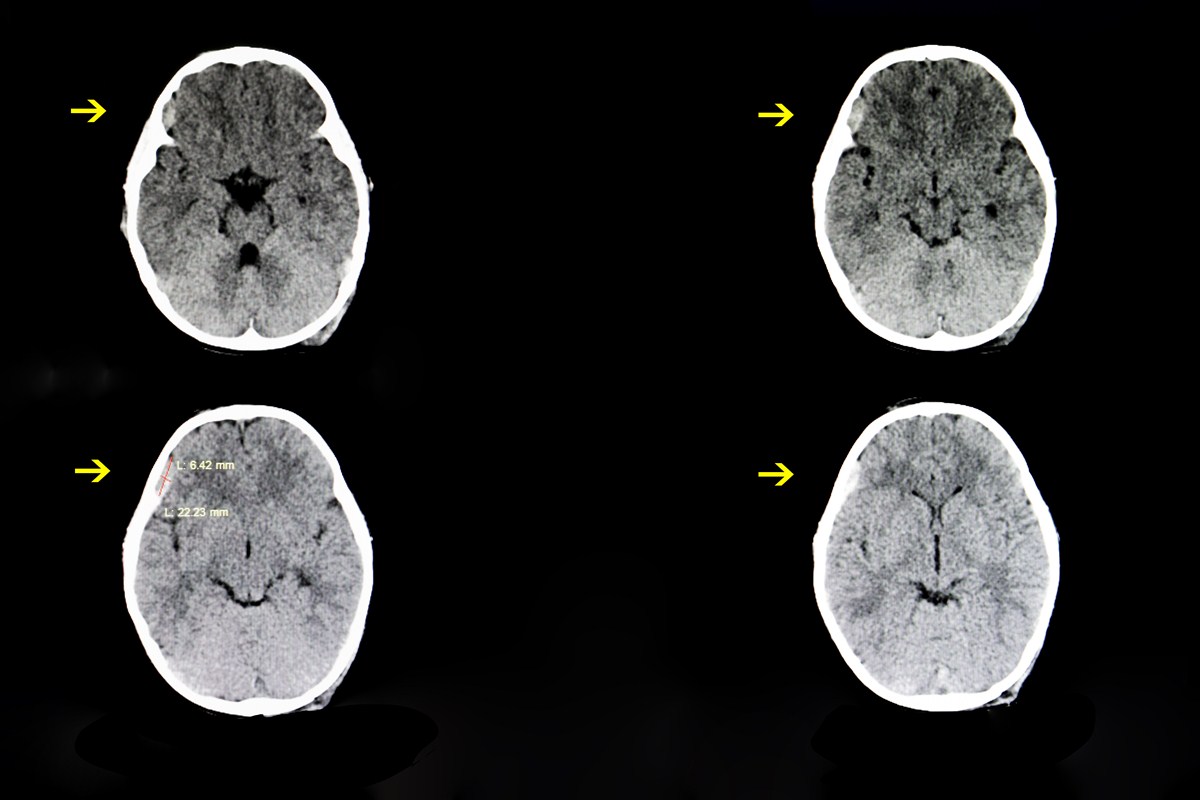

Chronic subdural hematomas are relatively common neurological conditions that can be seen secondary to chronic alcohol use, chronic pain-killer use or when dealing with cases of head trauma. In a good portion of these cases, some complications can lead to re-bleeding events or cerebrospinal fluid entrapment that can lead to altered mental status if the condition is not alleviated. Chronic subdural hematomas is a condition that is more prevalent as a patient ages and studies show that about 3 percent of patients over the age of 80 will suffer from them. [1]

Although the cascade of symptoms can be quite complex for this condition, the treatment option has always been quite straightforward. Burr hole surgery is the standard of care and essentially means that a small hole will be drilled into the surface of the skull in order to drain the blood that had been collected in the subdural space and evacuated to prevent from increased intracranial pressure. The question is if this is the best possible method available or is there an alternative treatment that can be just as effective.

Burr hole procedures are valuable in the clinical setting because they provide a quick solution to the underlying pathology and have been shown in studies to have low recurrent rates so patients will not need to have another operation in the future most of the time. Although there is some debate in medical circles about what type of drill bit and what location provides the best outcome for the patients, they determined that having a catheter placed on the frontal bones of the skull offered the best response rate. [2]

The radical nature of this procedure has left many patients and families hoping for a more conservative approach to manage subdural hematomas, and the medical community has not been deaf to these requests. When surgery is necessary, patients are now able to have newer craniotomy procedures called trephination where smaller holes and catheters are needed. This procedure results in a reducing in the possible bleeding secondary to the surgery the patient just had so it is much more attractive for patients and currently, about 85 percent of patients will have this type of operation when dealing with subdural hematomas.